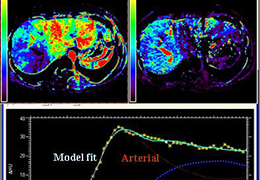

View X-Ray CT & MRI Scans Fast and Easily

Designed for surgeons, Pro Surgical 3D makes it easy to view patient scans quickly. Pro Surgical 3D facilitates the optimal 3D treatment and assessment workflows based on X-ray CT and MRI scans – and best of all, it’s FREE!

High-quality and fast 3D reconstruction and 3D rendering

Performs 3D reconstruction and volume rendering.

Side-by-side comparative assessment for pre- and post-operative scans.